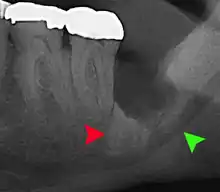

Panoramic radiograph of impacted lower wisdom teeth (green arrows) in a 26-year-old with dental caries (red arrows) on the adjacent teeth

The diagnosis of impaction can be made clinically if enough of the wisdom tooth is visible to determine its angulation, depth, and if the patient is old enough that further eruption or uprighting is unlikely. Wisdom teeth continue to move to the age of 25 years old due to eruption, and then continue some later movement owing to periodontal disease.[18]

If the tooth cannot be assessed with clinical exam alone, the diagnosis is made using either a panoramic radiograph or cone-beam CT. Where unerupted wisdom teeth still have eruption potential several predictors are used to determine the chance of the teeth becoming impacted. The ratio of space between the tooth crown length and the amount of space available, the angle of the teeth compared to the other teeth are the two most commonly used predictors, with the space ratio being the most accurate. Despite the capacity for movement into early adulthood, the likelihood that the tooth will become impacted can be predicted when the ratio of space available to the length of the crown of the tooth is under 1.[5]:141